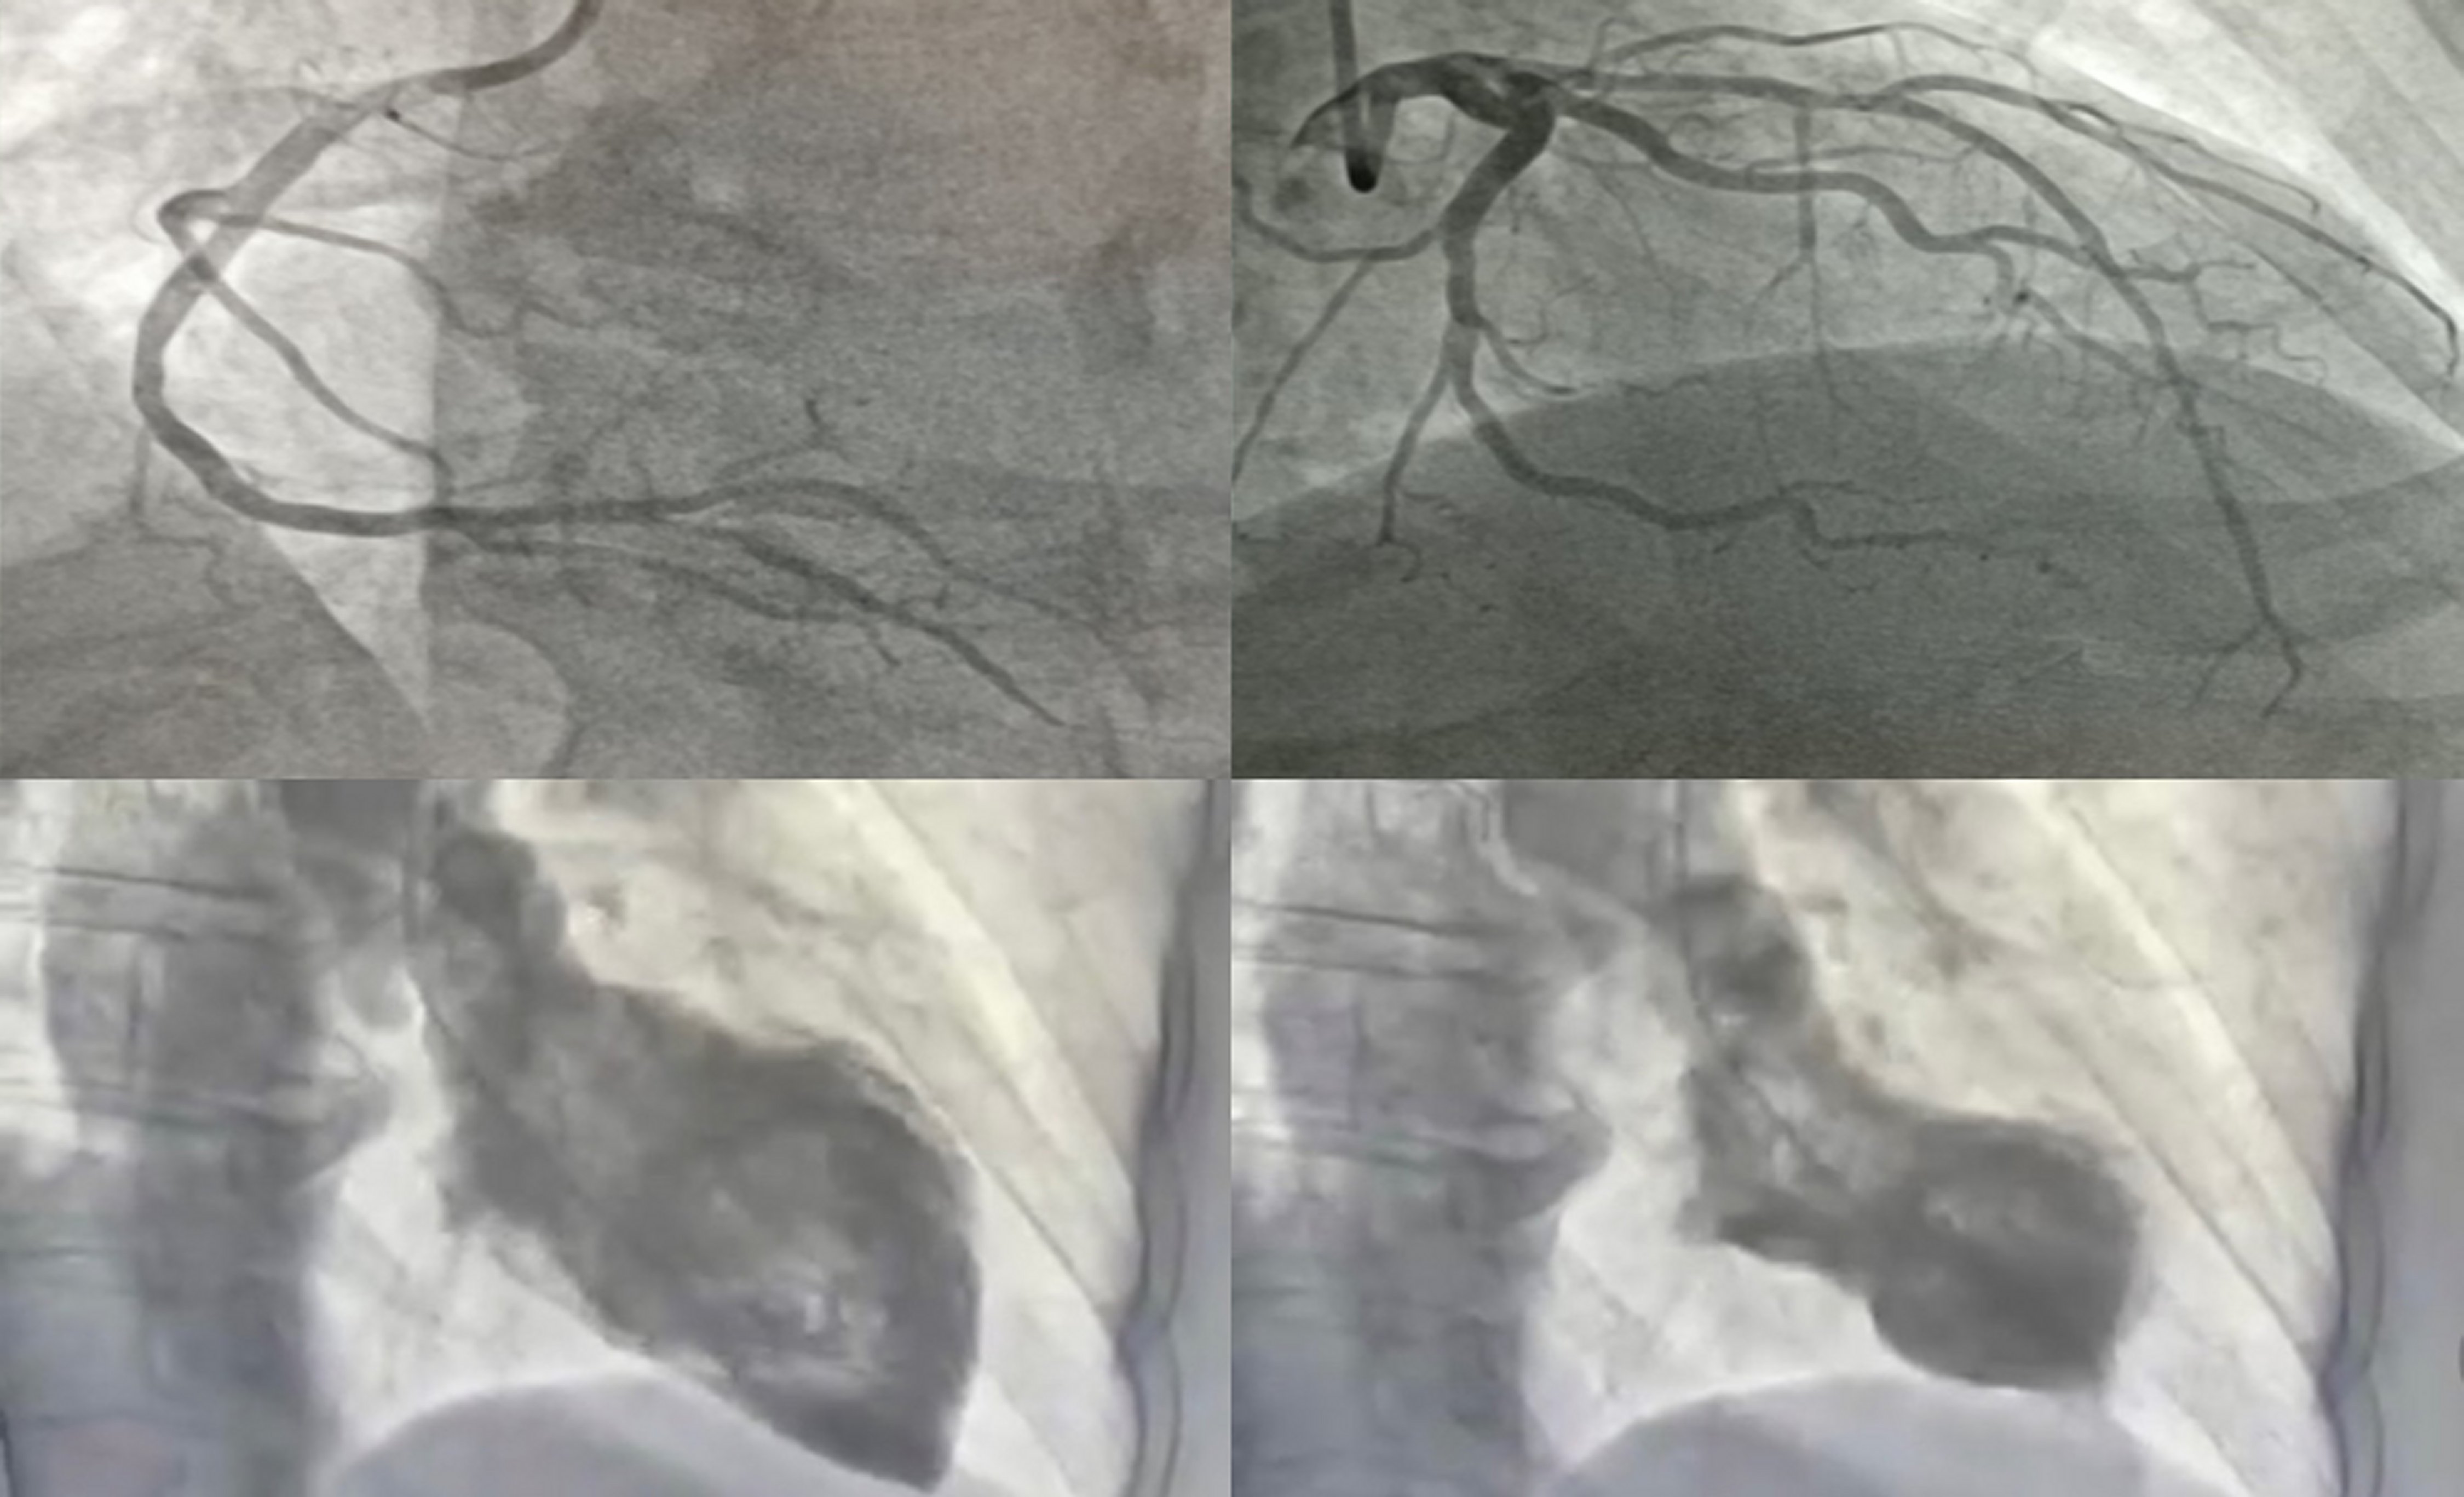

Coronary angiography was done due to the initial suspicion of acute coronary syndrome (ACS) and the results showed that the coronary tree was free of lesionsand ventriculography revealed significant ventricular dysfunction, with hypercontractility of the most basal segments and akinesia of distal ones, consistent with Takotsubo syndrome (Figure 3). These findings were also found in the Doppler echocardiogram.